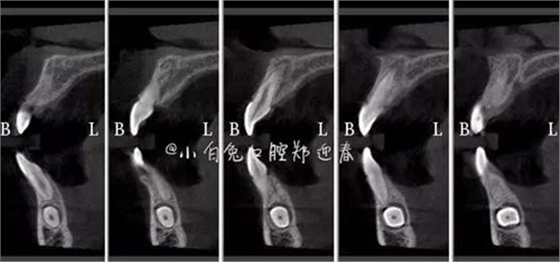

CBCT顯示

設計冠切的位置

橫斷牙冠,注意深度的把控

為了減少骨創(chuàng),“T”型分割牙冠